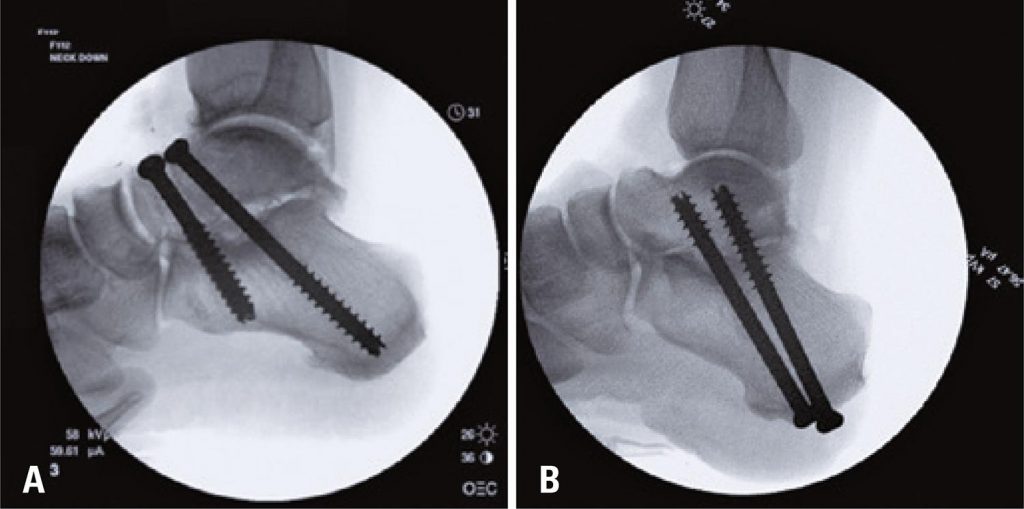

Eight matched pairs of cadaver feet underwent subtalar joint arthrodesis with two 7.3mm cannulated screws. Randomization was used to assign screw orientation, such that one foot in each pair was assigned dorsal to plantar screw orientation (DP Group), and the other foot, plantar to dorsal orientation (PD Group). Standard surgical technique with fluoroscopy was used for each approach. Following fixation, each specimen was loaded to failure with a Bionix ® 858 MTS device, applying a downward axial force at a distance to create torque. Torque to failure was compared between DP and PD Groups using Student’s t test, with p=0.05 used to determine statistical significance.